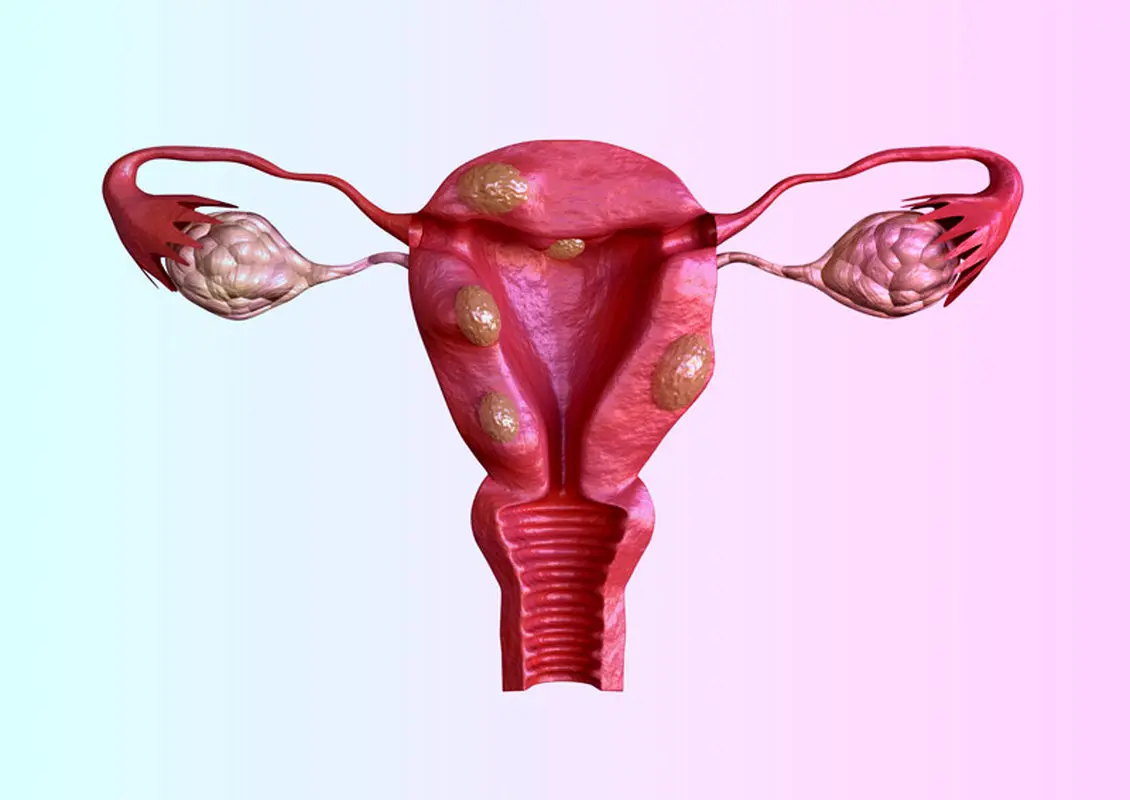

فیبرومهای رحمی از شایعترین تومورهای خوشخیم در زنان در سن باروری هستند که میتوانند باعث علائم ناخوشایندی مانند خونریزیهای شدید قاعدگی، درد لگن و مشکلات باروری شوند. در حالی که درمانهای پزشکی و جراحی برای فیبروم وجود دارد، اخیراً توجه به مداخلات غیرتهاجمی مانند ورزش به عنوان یک روش مکمل افزایش یافته است. این مقاله به بررسی نقش ورزش در مدیریت فیبرومهای رحمی، مکانیسمهای اثرگذاری و بهترین انواع فعالیتهای ورزشی برای این منظور میپردازد.

نشان داده شده که ورزش، سطح استروژن و پروژسترون را کاهش میدهد. ورزش منظم ممکن است با کاهش هورمونها و فیبرومها که اغلب توسط هورمونها تحریک میشوند، از رشد فیبرومها جلوگیری کند. مطالعات همچنین نشان میدهد که شاخص توده بدنی (BMI) بالاتر با رشد فیبروم مرتبط است. ورزش منظم در کاهش BMI تاثیر دارد، بنابراین میتواند رشد فیبروم را نیز کاهش دهد.

آمبولیزاسیون فیبروم نیز با محروم کردن فیبرومها از خونرسانی، آنها را کوچک میکند. بدون مواد مغذی و اکسیژن در خون، فیبرومها گرسنگی میکشند. آمبولیزاسیون یک درمان غیرجراحی است که فیبروم و علائم فیبروم را بدون نیاز به جراحی کاهش میدهد. فیبرومهایی که به درستی آمبولیزه شدهاند هرگز دوباره ظاهر نمیشوند و دوباره رشد نمیکنند.